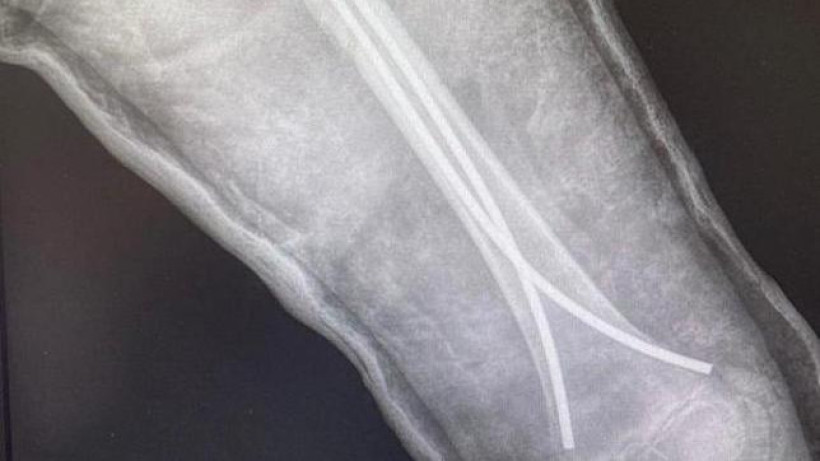

Фото: gov.kz

Технология остеосинтеза «гибкими гвоздями», или ТЭНами, заключается в том, что сломанную кость сопоставляют и прочно фиксируют при помощи специальных стержней, или «гвоздей». Снимают их только после полного сращения кости. Это технология исключила необходимость четырехнедельного нахождения на растяжке.

«Эта технология является золотым стандартом лечения диафизарных переломов трубчатых костей у детей до 12–13 лет. Она сокращает срок нахождения в больнице до 5 дней, исключает вторичное смещение костных фрагментов. Кроме того, нет необходимости часто повторять снимки. Еще один плюс – ранняя активизация. Так как перелом сопоставлен и зафиксирован, пациенты могут садиться, передвигаться», – поясняет заведующая отделением детской ортопедии Шолпан Мукашева.

Одному из пациентов отделения 12 лет. Ему установили ТЭНы на левой бедренной кости, перелом мальчик получил во время игры в футбол. В больницу пациент поступил со смещением отломков кости. Перелом сопоставили и зафиксировали, через несколько дней подросток будет готовиться к выписке. Самым маленьким пациентом с переломом бедра, которому установили ТЭНы в этом году, был малыш возрастом 1 год и 3 месяца.